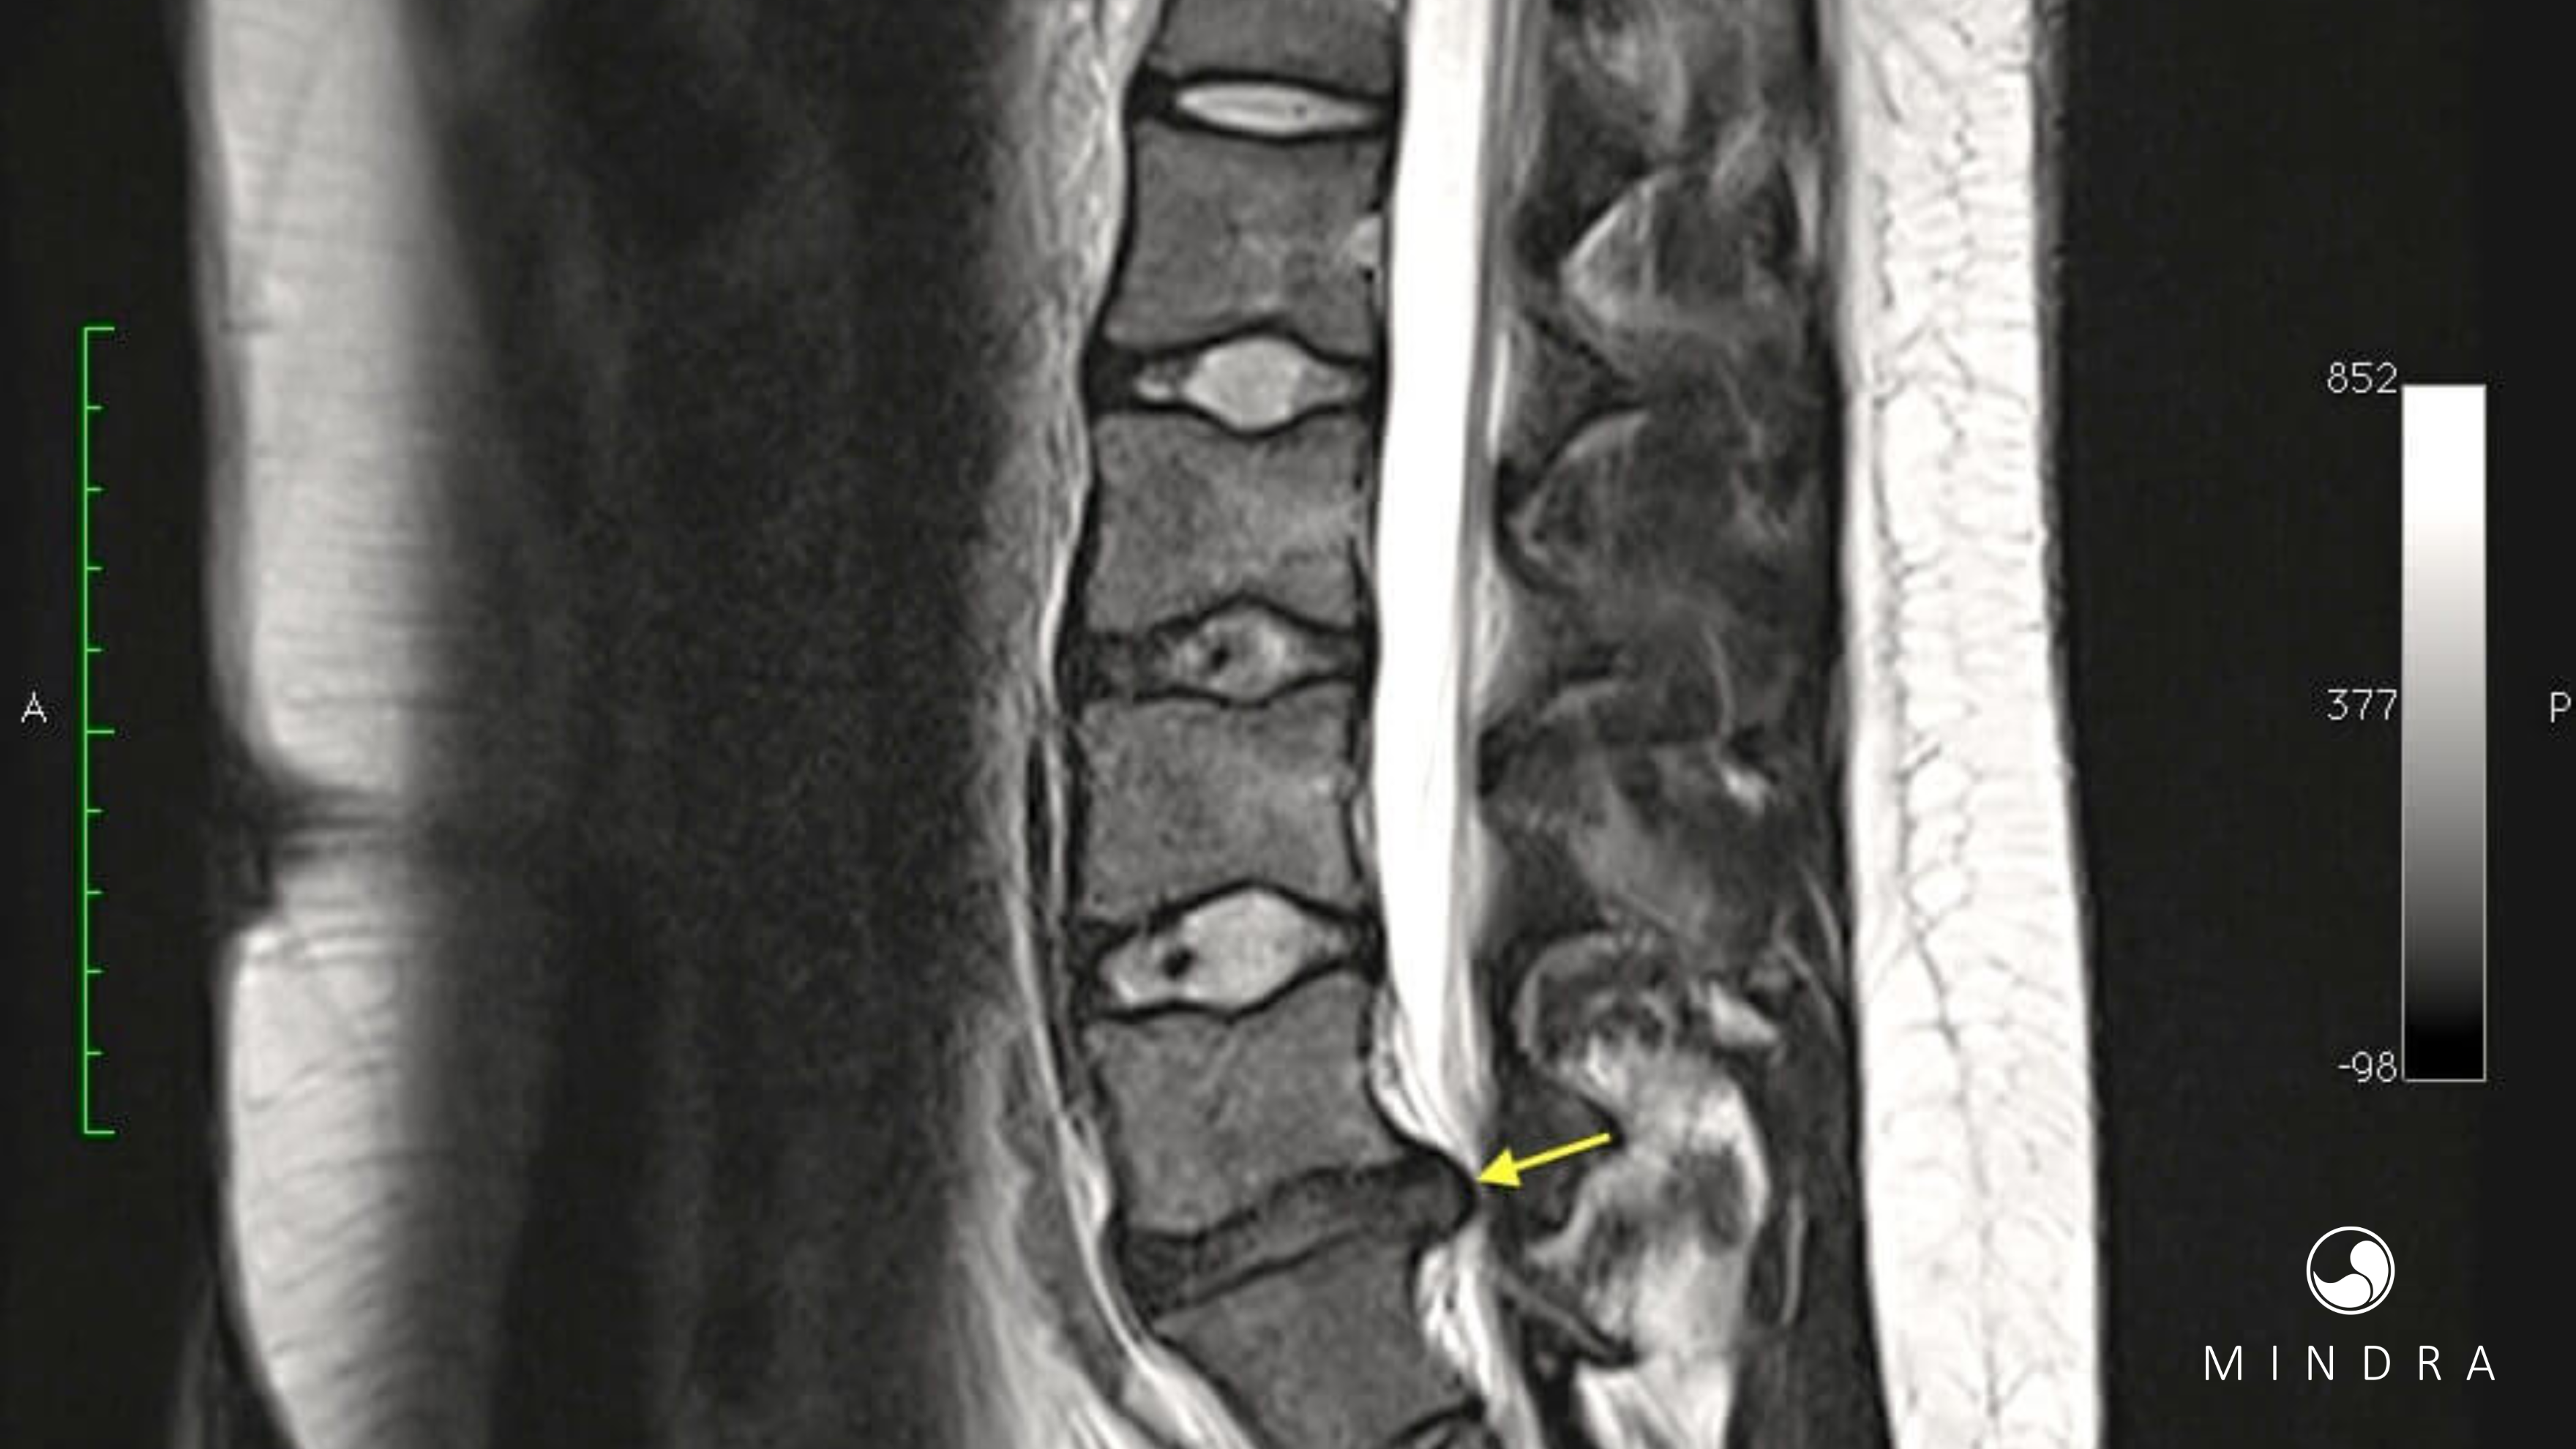

A hérnia de disco lombar é uma das causas mais comuns de dor nas costas e ciatalgia (dor que desce pela perna). A boa notícia é que a maioria das hérnias de disco NÃO precisa de cirurgia. Em grande parte dos casos, o corpo tem capacidade de se reorganizar, e o foco do tratamento é controlar a dor, proteger a função e ajudar a pessoa a voltar à vida ativa com segurança.

Nesse conjunto de estudos, os pacientes com hérnia de disco lombar aguda que receberam esse tipo de acupuntura tiveram, em geral, menos dor e melhor resposta clínica global do que aqueles tratados apenas com métodos convencionais (como medicação, fisioterapia isolada ou acupuntura “genérica”). Em termos simples: quando a acupuntura foi aplicada ao longo da linha média da coluna e região paravertebral, os resultados para dor foram melhores no curto prazo.